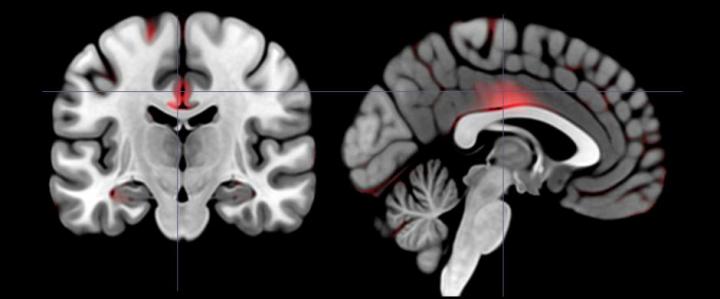

The subjects then underwent MRI scans designed to detect the volume of gray matter in different regions of their brain. From the psychological literature on extroversion, White and lead author Erica Grodin, a graduate student, knew they wanted to look in regions of interest such as the medial orbitofrontal cortex, which is involved in making choices based on reward, but they also cast a broader net of analysis across the whole brain using a technique called voxel-based morphometry.

As expected, they found that higher degrees of either kind of extroversion significantly correlated with higher gray matter volumes in the right and left medial orbitofrontal cortex, even after controlling for possible confounding factors such as age. But among the people with higher agentic extroversion scores, they also found several other regions that had significantly larger gray matter volumes: the parahippocampal gyrus (involved in learning and memory for reward); the precentral gyrus, cingulate gyrus, and caudate (involved in the cognitive control of behavior and the initiation, planning, and execution of voluntary movement toward goals); and, among the men in the study, the nucleus accumbens (involved in incentive reward).

So while both kinds of extroverts had higher volumes in one key brain region, agentic extroverts also had higher volumes in several other areas. White and Grodin found many of those other areas through the VBM analysis of the whole brain.